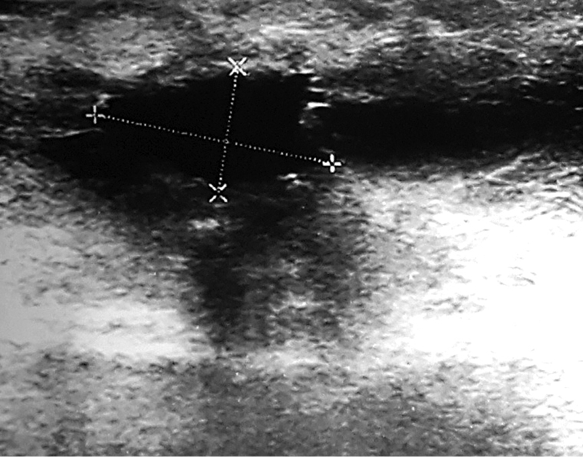

Fig. 1. The lesion was seen on ultrasound image

During physical examination a 2 cm hard, not tender, with ill-defined margins lump in the upper inner quadrant of the right breast has been found. There was no nipple retraction, discharge or skin change. A breast ultrasound showed a 1.24x0.85 cm suspicious ill-defined hypoechogenic lesion at 1 o’clock position of the right breast (Figure 1). Mammogram revealed a local hyperdense zone in the right breast (Figure 2). Histopathological examination of the tumour core biopsy material revealed desmoid type fibromatosis. The patient underwent wide local with clear margins excision of the lesion. Histopathological examination of surgical material confirmed desmoid type fibromatosis (Figure 3). Tumour was poorly demarcated, composed of spindle-shape myofibroblasts arranged in long sweeping fascicles. There was no mitotic activity. Immunohistochemical findings of the mass showed a focally positive reaction with beta-catenin, and a negative reaction for CD34, Desmin, CK. The patient did not require any adjuvant treatment. There was no recurrence after two years of follow-up.

Clinically breast fibromatosis presents as firm, painless mass [4, 8]. Nipple, skin retraction may be seen [2, 4, 8]. On ultrasound images, desmoid tumour typically appears as hypoechogenic, ill-defined mass [1, 8]. In our case, tumour also was firm, not tender, with echoscopically seen ill-defined margins.